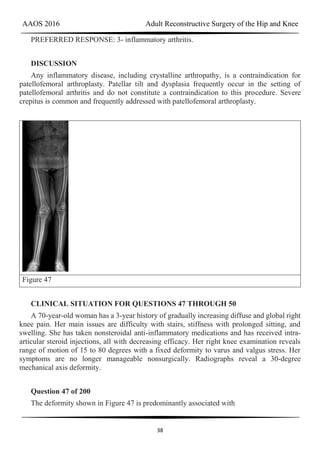

Figure 47

CLINICAL SITUATION FOR QUESTIONS 47 THROUGH 50

A 70-year-old woman has a 3-year history of gradually increasing diffuse and global right

knee pain. Her main issues are difficulty with stairs, stiffness with prolonged sitting, and

swelling. She has taken nonsteroidal anti-inflammatory medications and has received intra-

articular steroid injections, all with decreasing efficacy. Her right knee examination reveals

range of motion of 15 to 80 degrees with a fixed deformity to varus and valgus stress. Her

symptoms are no longer manageable nonsurgically. Radiographs reveal a 30-degree

mechanical axis deformity.

Question 47 of 200

The deformity shown in Figure 47 is predominantly associated with

AAOS 2016 Adult Reconstructive Surgery of the Hip and Knee

39

1- a hypoplastic lateral femoral condyle.

2- a contracted medial collateral ligament.

3- an excessive proximal tibial slope.

4- trochlear dysplasia.

PREFERRED RESPONSE: 1- a hypoplastic lateral femoral condyle.